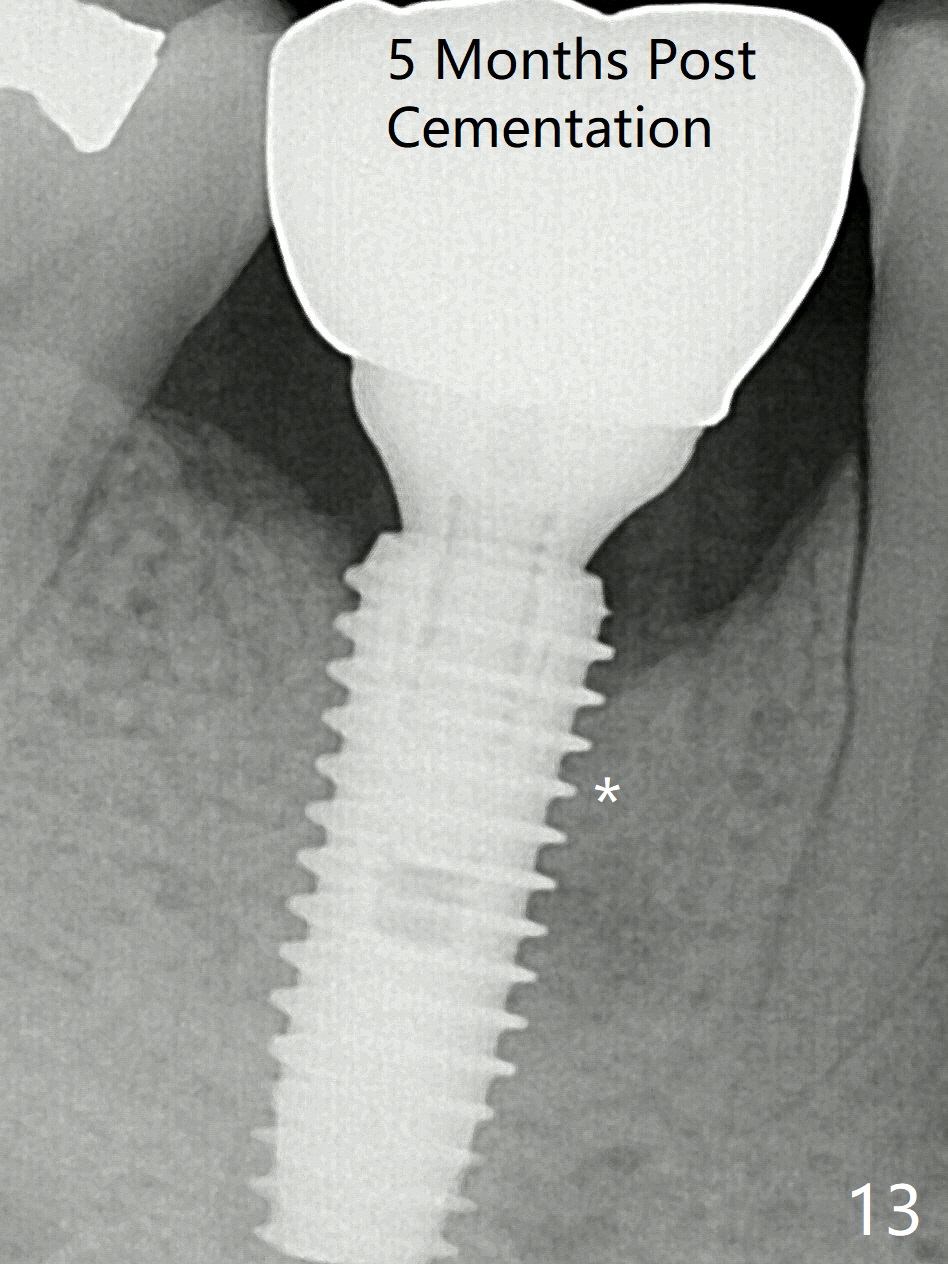

Preop oral Amoxicillin seems to be associated with reduction in the buccal and lingual (Fig.3 arrow) fistulae at #30, but there is mesiobuccal swelling (Fig.1 *) with 7 mm pocket (Fig.2). Osteotomy is initiated in the middle of the septum (Fig.3-5 S). As the osteotomy increases, it shifts mesially (Fig.6 arrow). Guided surgery is able to reduce shifting. A 5x13 mm implant is not seated completely (Fig.7) apparently due to osteotomy shifting. After removal of the bone from the osteotomy distally, the implant remains unseated with lower torque value (Fig.8). Following reuse of the 4.3 mm drill deeper by 1-2 mm, the implant is seated to a satisfactory depth (Fig.9 with increase in torque to 50 Ncm) with placement of Vera Graft (*) and a 7.5x4(3) mm abutment. After a second round of allograft placement (Fig.10 *), the implant is found to be 4 mm from the IAC. At the later stage of osteotomy, the coronal end of the septum is destroyed with loss of osteotomy depth landmark. It is apparent that the soft tissue landmark may be more reliable. The implant threads appear to be covered by the bone graft 3.5 months postop (Fig.11). The abutment is changed to 6.5x5(3) mm one before impression with minor margin prep. The bone density seems to increase 5 months postop, i.e., immediately post cementation (Fig.12) and 10 months postop (5 months post cementation (after retightening abutment), Fig.13 (*)). Periimplantitis develops mesiobuccally, consistent with bone loss 1 year 7 months post cementation (Fig.14 *); the implant seems to have been buccally placed. Bone graft is necessary with PRF or GEM21S if the vein is small and 6-month membrane with a hole around a 7.5x4(4) cemented abutment for easy wound closure. Take 5x5 CM CBCT to determine which wall has defect, buccal or lingual. Check mesial contact. If so, remove the crown, reseat the abutment (possible incomplete seating) and re-impress after bone graft.